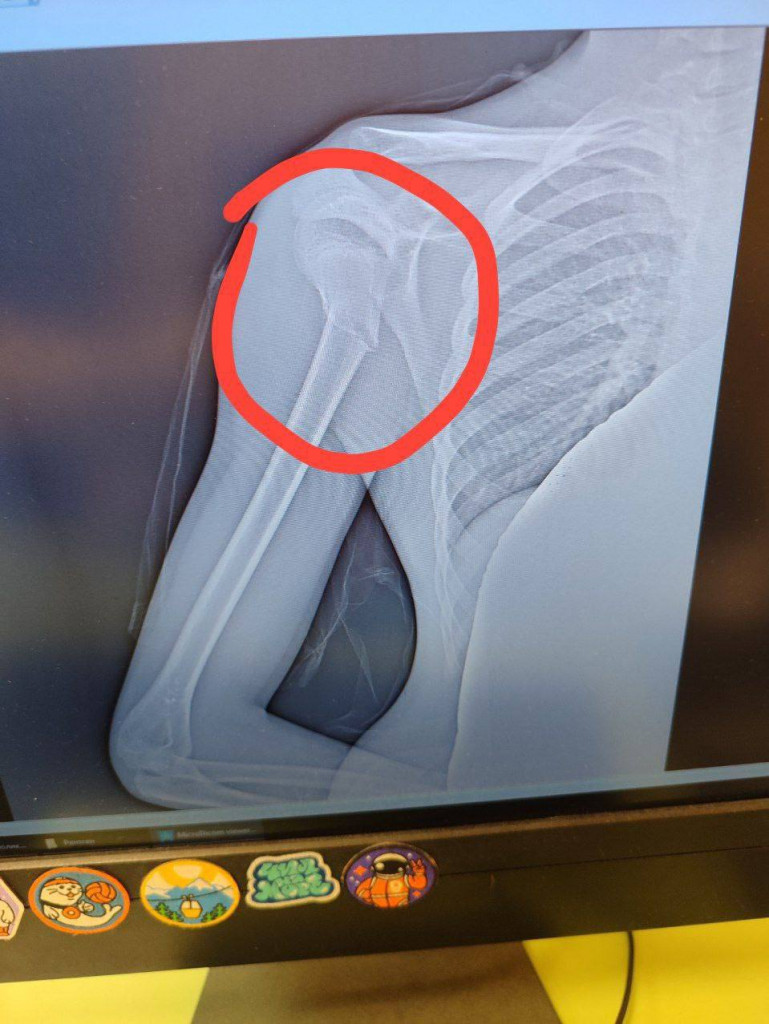

Мать пострадавшего написала в соцсетях, что после случившегося ребенку вызвали скорую, медики диагностировали перелом со смещением. На снимке - перелом плечевой кости. Женщина ищет обидчика и планирует обращаться в полицию.